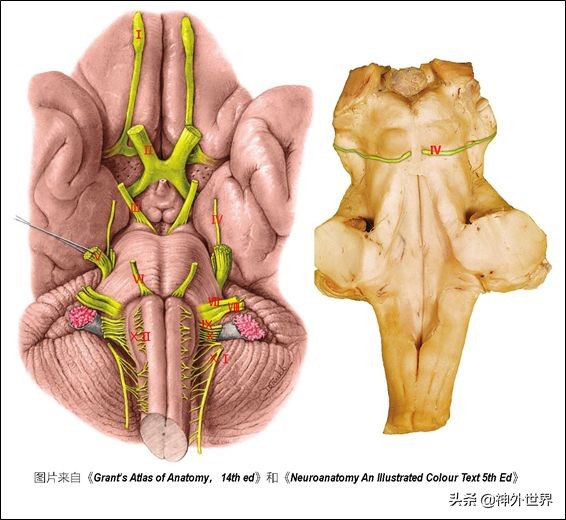

- 颅神经核与颅神经:①一核一功能,一神经一区域。②与脑干连接的10对颅神经中:动眼、滑车、外展神经支配眼球活动;迷走神经迷走至躯干的内脏支配内脏活动;舌咽、迷走、舌下与吞咽功能相关→后组颅神经麻痹致吞咽困难。③胚胎早期功能类别相同的颅神经核集中在一起形成个细胞功能柱,功能有7类,但功能柱只有6个(因为特殊内脏感觉和一般内脏感觉同在孤束核)。以后功能柱断裂成18个颅神经核。但神经核的排布还是按7个细胞功能柱的规律排列的(界沟以内为运动,界沟以外为感觉,具体排布规律看下图)。

四、脑干与小脑之间的三个裂隙和三个神经血管复合体

- 中脑小脑裂——三叉神经小脑上动脉复合体。——第四脑室顶壁上半部与中脑顶盖之间。

- 脑桥小脑裂——小脑前下动脉-面听神经复合体——第四脑室外侧隐窝开口于此。

- 延髓小脑裂——小脑后下动脉-后组颅神经复合体——第四脑室顶壁下半部。